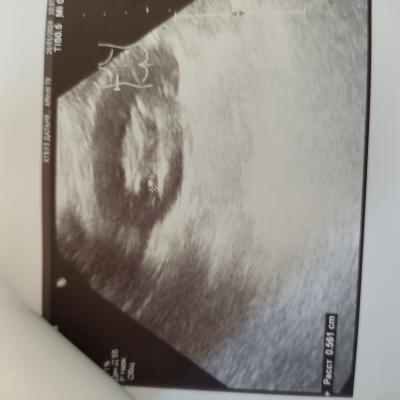

Дд. Помогите расшифровать УЗИ. Камень в почке, ужасные боли. Что можно сделать, чтоб облегчить их и ускорить выход камня? И выйдет ли каиень такого размера? Спасибо

Вам нужно начать с визита к врачу урологу на очный прием. Пройти обследование. Возможно потребуется выполнение компьютерной томографии для точной диагностики и точного выявления локализации камня и его размера. Без обследования, в первую очередь компьютерной томографии, принять решение о возможности или невозможности самостоятельного отхождения камня невозможно.